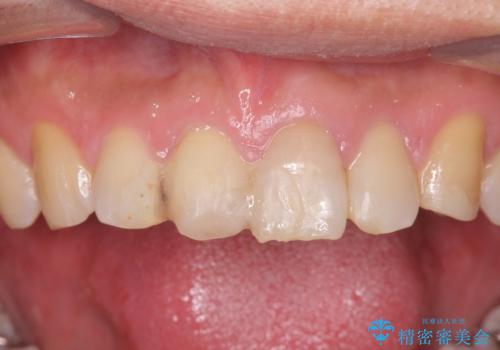

転んで前歯が欠けてぐらぐらに 歯の神経も死んでしまった

- 転倒して前歯を強打してかけてしまった、ぐらつくとのことで来院。

応急でみてもらった歯科医院で隣の歯と接着剤で留めてもらったとのこと。

歯の神経の状態を見たところ、前歯3本とも神経が死んでしまっていました。

根の治療を行い、ぐらつきに関しては様子を見て連結をするとのお話をさせていただきました。

結果ナイトガードの使用によりぐらつきはだいぶ回復してきたため連結はしていません。